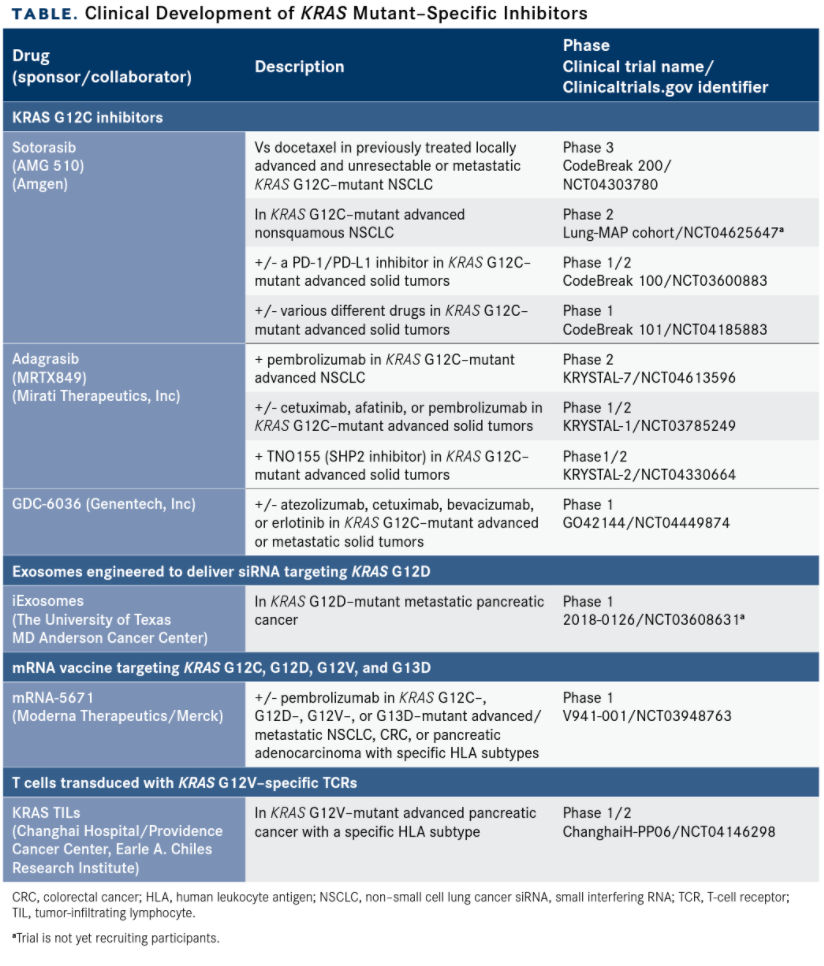

After decades of failed attempts to target the RAS pathway, which came to be thought of as undruggable, greater insight into KRAS biology has led to the discovery of potentially targetable pockets on the mutant protein.1,3,21 Signals of efficacy in several novel agents have spurred fresh industry research into KRAS-specific targets (TABLE).

Several small-molecule inhibitors of the KRAS G12C–mutant protein have been developed and represent a promising advance in the treatment of KRAS-mutant cancers. These drugs bind to a small pocket underneath the effector binding region that is only revealed in the GDP-bound form, locking the mutant protein in this inactive state.1,3

Leading the pack is sotorasib, which investigators are evaluating in clinical trials in various KRAS-mutant cancers and which has advanced the furthest in NSCLC. Amgen submitted an NDA for sotorasib for the treatment of patients with KRAS G12C–mutant advanced NSCLC, according to a company announcement in December 2020.2

The submission is supported by phase 2 results from the ongoing CodeBreak 100 study (NCT03600883) in patients with disease progression after up to 3 prior lines of therapy. Orally administered sotorasib resulted in median progression-free survival of 6.8 months (95% CI, 5.1-8.2) with a confirmed objective response rate (ORR) of 37.1% among 124 patients. The findings were presented during the International Association for the Study of Lung Cancer World Conference on Lung Cancer in January 2021. The phase 3 confirmatory CodeBreak 200 trial in NSCLC recently began enrolling patients (NCT04303780).22,23

Mirati Therapeutics has also advanced its KRAS G12C inhibitor into clinical trials. As of August 30, 2020, 108 patients with previously treated advanced solid tumors (79 NSCLC, 22 CRC, and 7 other) had been treated with adagrasib 600 mg twice daily.6,7

The ORR in patients with NSCLC was 45%, including 5 unconfirmed partial responses (PRs), and in patients with CRC it was 17%. Confirmed PRs also were observed in 1 patient with endometrial cancer and in another with pancreatic cancer. Treatmentrelated adverse events included nausea, diarrhea, vomiting, fatigue, and increased alanine aminotransferase levels.6,7

TABLE. Clinical Development of KRAS Mutant–Specific Inhibitors

In a presentation at the RAS Targeted Drug Development Summit in September 2020, Steve Kelsey, president of research and development at Revolution Medicines, reported promising preclinical data for the company’s KRAS G12C(ON) and KRAS G12D(ON) inhibitors.26

Mirati is developing a KRAS G12D inhibitor, MRTX1133, which has demonstrated significant tumor regression in preclinical models. The company reportedly plans to file an investigational NDA with the FDA in the f irst half of 2021.14

They are similar to liposomes and other nanoparticle drug delivery systems in development, but they express the cell-surface protein CD47, which generates the so-called “don’t eat me” signal upon receptor binding. This allows them to avoid phagocytosis by immune cells, which should extend their half-life in the circulation. Preclinical development of iExosomes targeted KRAS G12D–mutant pancreatic cancer, and a phase 1 trial (NCT03608631) is underway.12,13

Also in clinical trials are several agents based on immunotherapeutic strategies targeting mutant KRAS proteins. Merck and Moderna are developing mRNA-5671, a cancer vaccine designed to target the KRAS G12C, G12D, G12V, and G13D mutants. Meanwhile, the use of adoptive cell therapy is also being explored, with genetically engineered T-cell receptors that recognize the G12V and G12D mutants transduced into tumor-infiltrating lymphocytes and peripheral blood lymphocytes, respectively.28